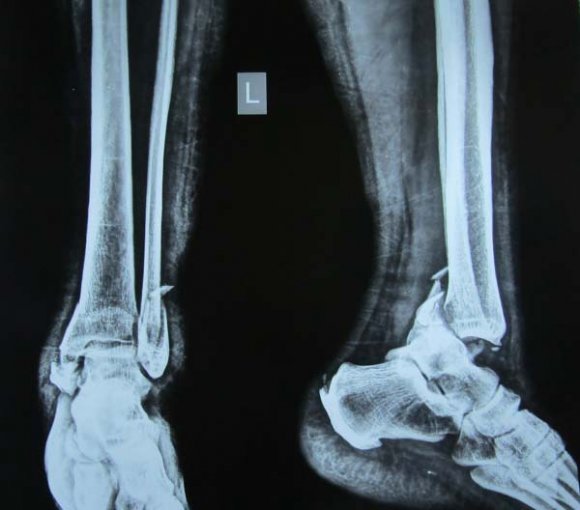

A 26-year-old man alleged history of the road traffic accident. He was came to the emergency department, and done Roentgenogram and CT scan that displayed combined ipsilateral fractures of the scaphoid and comminuted distal end radius fracture. The scaphoid fractures were typed A according to the Herbert classification system, and the distal radial fractures were type C (23-C3) according to the AO classification system (Figure 1 & 2). Open reduction of the intra-articular distal radius fracture and the scaphoid fracture was performed under regional anesthesia. Initially, we fixed the distal end radius from the dorsal side using locking plate via the dorsal approach then dissection was made between the flexor carpi radialis and palmaris longus tendons, and it was extended 3 cm distal to the wrist flexion crease to expose the scaphoid. The flexor pollicis longus tendon was retracted in the direction of the radius, while the median nerve and other tendons were retracted in the direction of the ulna, revealing the pronator quadratus. Next the distal end radial borders of the pronator quadratus were raised and retracted in the direction of the ulna to expose the distal radius. First, the scaphoid fracture was fixed with a Herbert screw next open reduction and internal fixation of the distal end radius was performed with volar approach with the locking plate (Figures 3).